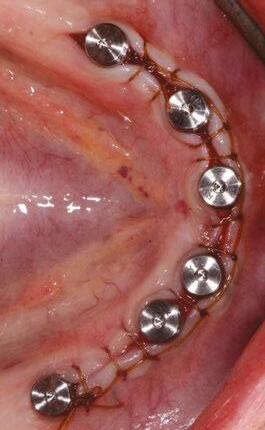

Horizontal mattress sutures

Horizontal mattress sutures are a technique used to close wounds under tension, such as those in the oral cavity. This technique involves placing stitches parallel to the incision, with each stitch passing through the tissue on either side of the incision (Figure 7). The mattress is typically the first suture throw to help close a wound, finished with either of the two previously dis-

cussed techniques. Its ability to reduce tension vectors across the incision line is key to its success in postoperative implant surgery.

Benefits of horizontal mattress sutures

1. Effective at closing wounds under tension.

2. Minimal tension on the wound edge.

3. Reduces the risk of wound dehiscence.

4. Helps to maintain downward pressure on a membrane and bone graft.

Technique

1. Begin with a bite 7 mm to 10 mm apical to the incision line (typically at the mucogingival junction) on the distal buccal of the incision.

2. With your next bite, exit the lingual tissue at similar depth to the initial buccal bite.

3. Re-bite the lingual tissue 5 mm to 10 mm mesial at the same depth.

4. Exit the buccal tissue perpendicular to the third bite — the four bites now forming a square with two threads crossing the crest/membrane.

5. Tie with a surgeon’s knot and any additional throws as needed depending on the suture material.

Building on the basics

Let’s review a recent case that showcases the rationale and techniques of the top three. It is common to utilize several suturing techniques in surgical closure, especially in larger grafting cases. In the following case, a lateral sinus lift was performed, and all three techniques were used to their full effect. Simple interrupted sutures are used to close small incisions and place tissue margins accurately back in place; horizontal mattress sutures are used to hold membranes in place and relieve tension over the incision line, and running interlocking continuous sutures are used to close longer incisions with watertight closure for maximum healing potential via primary closure.

A patient presented with a failing bridge on the upper left that is supported by three mini implants. The implants directly perforate the sinus and only ~2mm of residual bone height remains on the crest (Figure 8). The mini implants were removed, and a

25 endopracticeus.com Volume 16 Number 2 CONTINUING EDUCATION

Figures 7A and 7B: Horizontal mattress sutures are useful for helping to secure membranes in grafting situations and relieving tension in longer span incisions Figures 8A and 8B: The pre-op condition of the patient with mini implants engaging minimal bone and perforating the sinus. The patient’s implant supported bridge was loose and causing discomfort Figure 9: A periosteal biting mattress engages only the periosteum in the buccal vestibule and exit and re-enters on the lingual tissue, helping to secure the membrane tightly over the window and crest

Figure 10: Simple interrupted, papilla sling, and horizontal mattresses can be seen to achieve primary closure without any sutures over the main body of the incision. Passive closure requires that closure is obtainable without tension directly over the incision line, as seen here

lateral window sinus lift was performed. Over the window and crest, a pericardium membrane was positioned to close all perforations into the sinus. Pericaridum membranes are resorbable membranes made from either human or porcine pericardium. The tissue that surrounds the heart is known to be extremely resistant to tearing (a leading reason for pericarditis being potentially fatal), and facilitates great handling properties as a dental material. It can be easily tacked or sutured, and maintains its shape memory for ease of placement over a defect. A periosteal-biting mattress suture is thrown first to help pin the membrane down on the buccal plate and crest (Figure 9). Next, simple interrupted sutures are used to put the vertical incision in the posterior back in position and the vertical incision in the anterior. Third, a papilla sling is used mesial to tooth No. 11 to tightly reposition the gingiva around the canine. A papilla sling suture functions by using a tooth as a pivot point to “sling” around and help reapproximate tissue. Only the buccal papilla are engaged, and the suture is passed underneath proximal contacts (if necessary) to facilitate wrapping around the lingual of the tooth. This suture is very useful for coronally advancing flaps or maintaining the coronal position of papillas after flap release. Fourth, a horizontal mattress suture is placed at the depth of the mucogingival junction to help approximate the flap margins, relieve tension at the incision line, and evert the tissue (Figure 10). Lastly, a PTFE running double-interlocking continuous suture is used to complete the final closure of the surgical site (Figure 11).

Two weeks post-op photos show great tissue response and health thanks in large part to meticulous suturing of the case (Figure 12).

Conclusion

Proper suturing technique is essential for successful dental procedures. By understanding the benefits and techniques of the top three dental suturing techniques, dentists can choose the appropriate technique for each procedure and promote faster healing, reduce the risk of infection, and minimize discomfort and bleeding for the patient.

REFERENCES

1. Moy RL, Waldman B, Hein DW. A review of sutures and suturing techniques. J Derma-

tol Surg Oncol. 1992 Sep;18(9):785-795. doi: 10.1111/j.1524-4725.1992.tb03036.x. PMID: 1512311.

2. Yag-Howard C. Sutures, needles, and tissue adhesives: a review for dermatologic surgery. Dermatol Surg. 2014 Sep;40 Suppl 9:S3-S15. doi: 10.1097/01.DSS. 0000452738.23278.2d. PMID: 25158874.

3. Moy RL, Lee A, Zalka A. Commonly used suturing techniques in skin surgery. Am Fam Physician. 1991 Nov;44(5):1625-34. PMID: 1950960.

4. Davis B, Smith KD. Oral Surgery Suturing. [Updated 2023 Jan 25]. In: StatPearls [Internet]. Treasure Island (FL): StatPearls Publishing; 2023 Jan-. Available from: https://www. ncbi.nlm.nih.gov/books/NBK572089/.

5. Romeo A, Rocha CL, Fernandes LF, Asencio FA, Zomer MT, Fujimoto C, Ussia A, Wattiez A, Koninckx PR, Kondo W. What is the Best Surgeon’s Knot? Evaluation of the Security of the Different Laparoscopic Knot Combinations. J Minim Invasive Gynecol. 2018 Jul-Aug;25(5):902-911. doi: 10.1016/j.jmig.2018.01.032. Epub 2018 Feb 5. PMID: 29421249.

26 Endodontic Practice US Volume 16 Number 2 CONTINUING EDUCATION

EP

Figure 11: Final closure finished with interlocking continuous PTFE sutures for watertight secure closure Figures 12A and 12B: Two week post-op reveals minimal erythema and maintained tissue closure

Continuing Education Quiz

The importance of suturing in dental implant surgery

VORHOLT

1. Sutures help to _________.

a. hold the gingiva in an ideal place

b. promote healing

c. prevent infection

d. all of the above

2. The ideal suture material should be ________.

a. strong

b. flexible

c. biocompatible

3. Monofilament sutures have and therefore prohibit or vastly lessen bacterial migration along the length of the suture.

a. smooth microstructure

b. rough microstructure

c. multiple filaments

d. braided structure

4. (Regarding insertion of the suture needle into the tissue) Approaching the tissue at ______ can lead to shallow bites, torn tissue, and poor adaptation of the incision line.

a. an acute angle

b. an obtuse angle

c. a right angle

d. reflex angle

5. The Castroviejo-style needle holder is held in a palm grasp and is generally meant for use with thicker tissue and suture materials, while the Mathieu is a more delicate instrument more widely used with finer suture materials 5-0 and thinner.

a. True

b. False

6. Sutures with _______ should be cut longer to avoid irritation to the adjacent oral tissues and avoid early unraveling of the knots.

a. a braided shape

b. low shape memory

c. high shape memory

d. a rougher texture

Each article is equivalent to two CE credits. Available only to paid subscribers. Free subscriptions do not qualify for the CE credits. Subscribe and receive up to 16 CE credits for only $149; call 866-579-9496, or visit https://endopracticeus.com/ subscribe/ to subscribe today.

n To receive credit: Go online to https://endopracticeus.com/continuingeducation/, click on the article, then click on the take quiz button, and enter your test answers.

AGD Code: 690

Date Published: June 16, 2023

Expiration Date: June 16, 2026

2 CE CREDITS

7. ________ help to distribute the tension evenly along the incision, reducing the risk of wound dehiscence and promoting faster healing.

a. Simple interrupted sutures

b. Interlocking continuous sutures

c. Horizontal mattress sutures

d. Purse-string sutures

8. With simple interrupted sutures, cut the ears of the suture 5 mm minimum to avoid early untying of the suture material.

9. __________ reduce trauma to the tissue by minimizing the number of times the needle passes through the tissue.

d. Buried sutures

10. _________ help to maintain downward pressure on a membrane and bone graft.